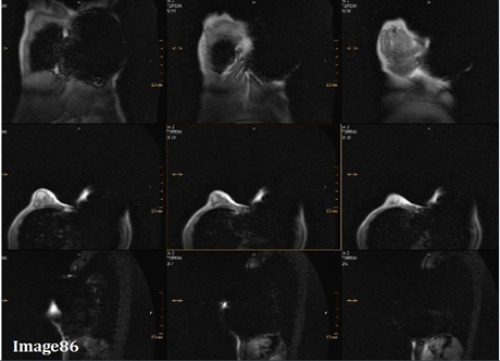

Image 86 is an example of which kind of artifact?

A. Motion/ghosting in the phase direction

B. Gibbs truncation

C. Dielectric effects

D. RF zipper

E. Magnetic susceptibility